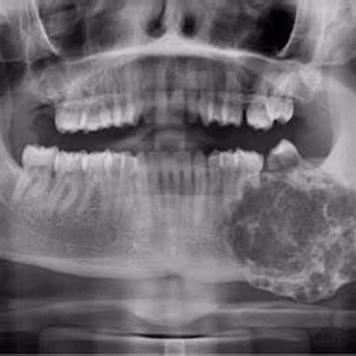

Diagnóstico e Tratamento de Tumores

Diagnóstico preciso, tratamento seguro e reconstrução cuidadosa.

Lesões e tumores da face e da cavidade oral exigem atenção especializada, diagnóstico precoce e planejamento criterioso para preservar função, estética e qualidade de vida.

Atuo no diagnóstico e tratamento de lesões benignas e malignas, com abordagem individualizada e integração com outras especialidades quando necessário.

Atuação inclui: